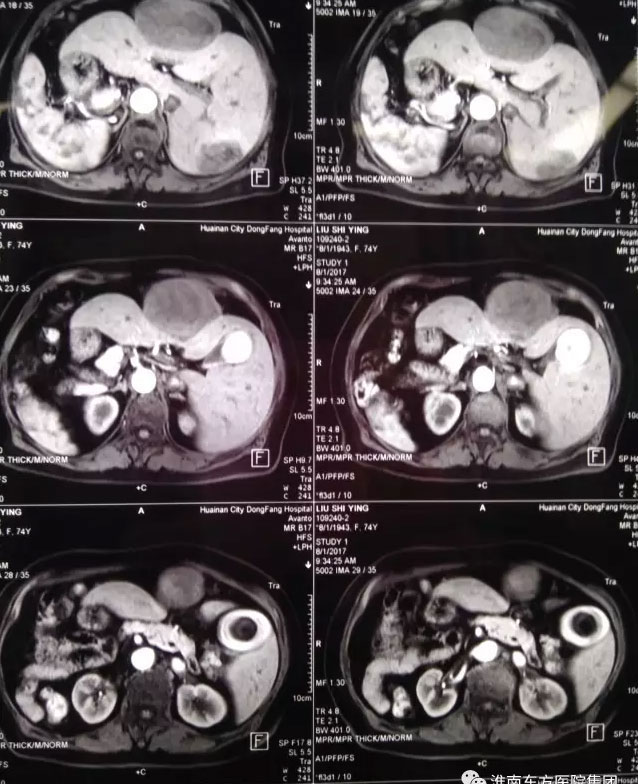

这位病人是75岁的刘老太大,长期居住黄山市,无意发现左侧上腹部“拳头”大小包块伴有隐痛,在当地中医院就诊,检查提示“肝脏多发肿瘤,胆囊内充满结石,右位心,冠心病”。因未接触过如此罕见疑难疾病而建议转上海、北京等上级医院治疗。病人子女在我市工作,抱着一线希望,带着老人来到我院肝胆胰外科。入院后完善相关检查,很快明确了诊断:肝脏IV、VII段两处肿瘤(原发性肝癌),最大的约10cm,胆囊充满性结石伴胆囊炎,冠心病,心律失常,高血压病,器官反位(镜面人)。虽然总院肝胆胰外科有着每年数百例肝胆手术的经验,但如此罕见变异,合并多种基础疾病,高龄的肝脏恶性肿瘤病人,尚属首次接诊,并无成功经验可循。

接诊后,江永强院长高度重视,提请医务处胡伟科长,组织全院疑难肿瘤病人多学科团队(MDT)会诊讨论。多位专家一致认为手术指征明确,但手术难度极高,麻醉管理难度较大,围手术期风险及并发症发生率高。尤其采用腹腔镜微创的方法,更是奇思妙想,大胆创新的思维。普外一科肝胆胰病区徐友标、张军、顾冕三位专家在术前翻阅了大量国内外关于“镜面人”手术的文字和录像资料,积极准备术中突发状况预案,并模拟进行演习。一切充分准备就绪后,手术于8月17日上午进行,徐友标主任亲自主刀,张军、顾冕两位医师配合,麻醉科刘伦主任主麻。术中在病人腹部五处布孔(每个孔约0.5-1cm)。徐主任采用反向操作及反手游离,经过三个小时紧张细致的操作,成功为病人实施“腹腔镜下肝脏IV、VII段两处肿瘤切除+胆囊切除术”。术中失血极少,麻醉平稳,病人在SICU(外科重症监护室)过渡一天后,即转回肝胆胰病房。次日刘阿姨已经进流质饮食,并可以适当活动,微创手术带给她的术后疼痛感觉微乎其微,刘阿姨和子女都难以相信,经历了如此高难度的大手术。